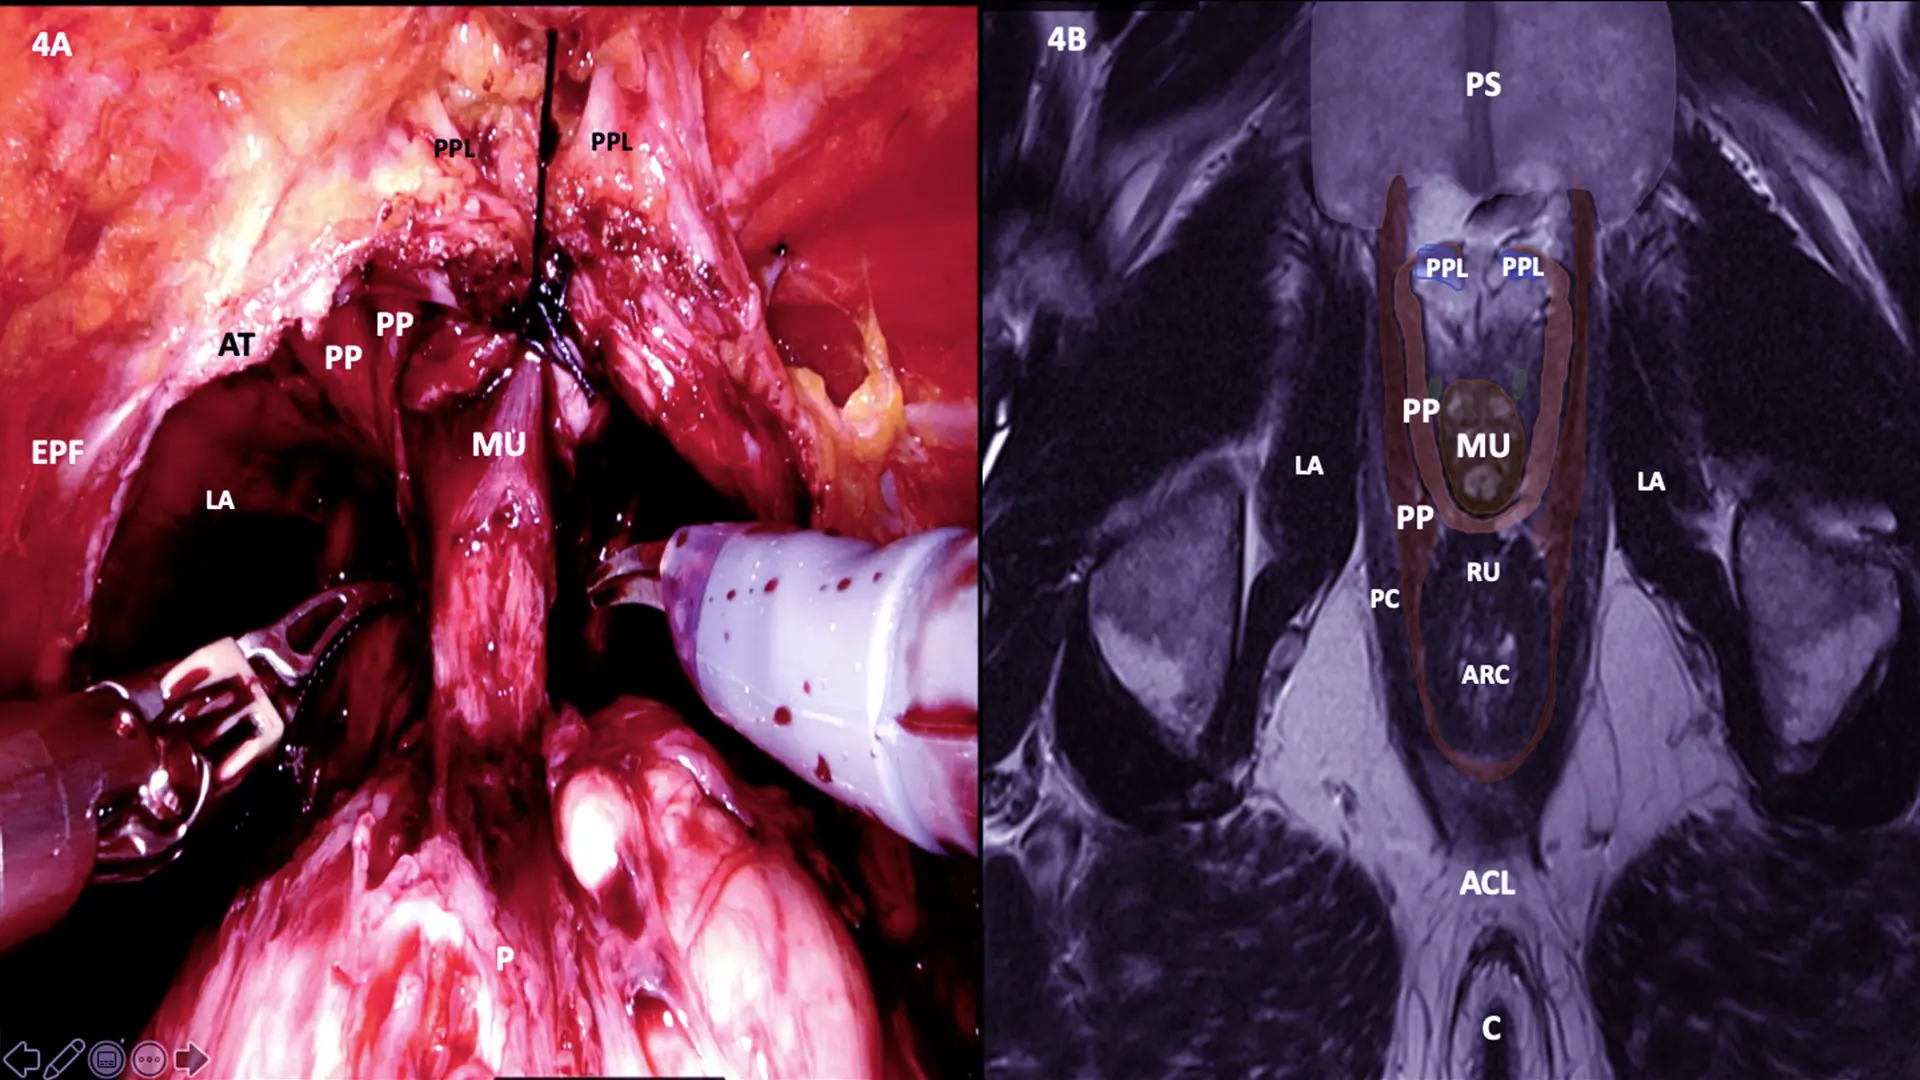

Upon removal of the prostate, the preserved tissue has a “hood-like” appearance, comprised of the detrusor apron, arcus tendineus, puboprostatic ligament, anterior vessels, and some fibers of the detrusor muscle. The hood effectively encloses and protects the membranous urethra, external sphincter, and supportive structures.

Sketch demonstrating Hood surgical anatomy. Anatomical components of Hood surrounds and safeguards membranous urethra and external urethral sphincter and thereby urethrovesical anastomosis.

MRI Cross section at A line with Surgery still Image

MRI Cross-section at B line with Surgery still image